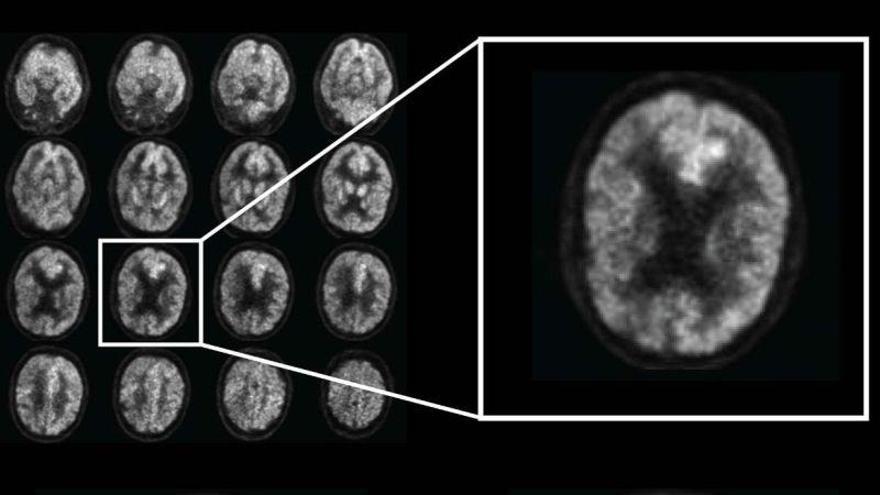

Un nuevo método para aumentar la eficacia de los nanomedicamentos indicados contra el glioblastoma multiforme, uno de los tumores cerebrales más mortales, fue descubierto por un equipo de la Academia Sínica, la principal institución de investigación de Taiwán, con sede en Taipei.

Se espera que este avance permita un mayor suministro de diversas nanomedicinas al cerebro. El líder del equipo, Patrick Hsieh, declaró que el glioblastoma es uno de los cánceres de cerebro más comunes y agresivos en el mundo, y tiene una tasa de supervivencia de cinco años inferior al 10 por ciento.

Esto se debe a la rápida evolución del tumor y la falta de un método eficaz para suministrar medicamentos de quimioterapia a través de la barrera hematoencefálica. Los resultados en las pruebas en cerdos son una señal positiva de que la técnica puede aplicarse con éxito a los humanos, agregó Hsieh.